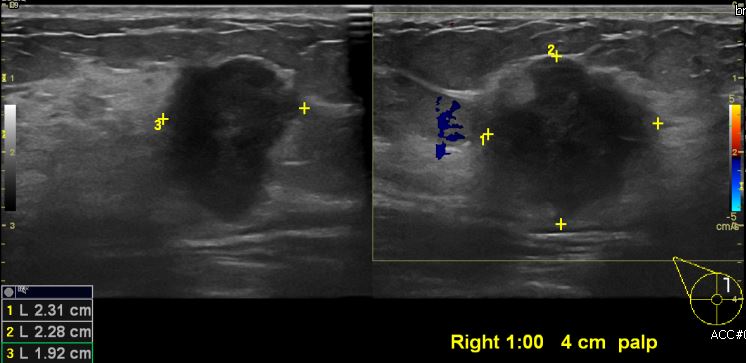

우측 유방에 만져지는 멍울로 내원하신 50대 여성분으로  본원 초음파상 우측유방 1시 방향에서 4cm 떨어진 거리의 만져지는 멍울 조직검사 시행하여 우측 침윤성 유관암 진단 되었습니다.